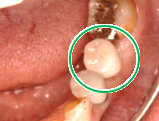

Before

青丸の部分を削り取りました

After